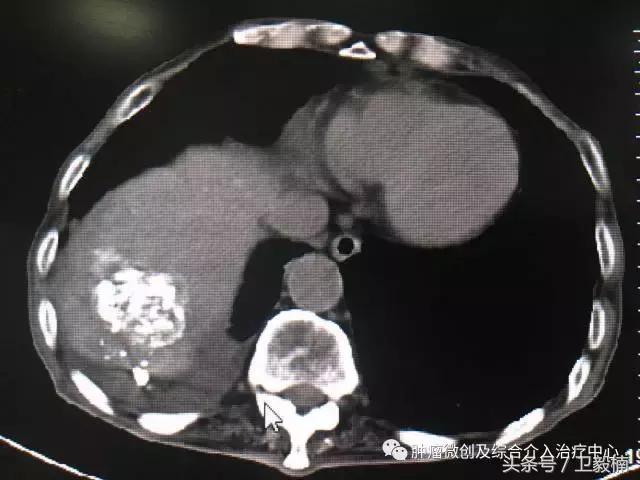

上腹部CT提示:肝脏占位破裂出血。